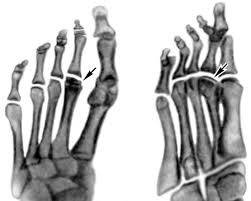

Остеохондропатия кісток – захворювання, що виявляється переважно у віці 7-25 років. Період розвитку найчастіше